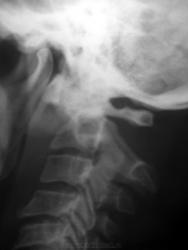

Неумная шутка коллег по работе в теплице - приставленная с другой стороны дверей лестница. Шутка удалась - при открывании дверей лестница упала на голову. Есть один снимок.

Интересный случай. Случай можно назвать - "Развод зуба с телом".

Атланто-аксиальная дислокация. Как ни всматиривалась, так и не удалось хорошо разглядеть зубовидный отростокНедоволен.

Атлант цел. В таких случаях возможны два варианта: перелом зубовидного отростка или разрыв связок сустава Крювелье.

Умозрительно, скорее второе.

Здесь так: поперечный перелом основания зуба С2, зуб развернуло в сагиттальной плоскости на 90 градусов кпереди, так, что он своим основанием контактирует с суставной поверхностью сустава Крювелье со стороны С1. Так что и разрывы связок там неизбежны. Подвывих С1 кпереди по отношению к С2 на 12-14 мм.

Как это удалось выяснить? На представленном снимке невозможно различить верхушку и основание зуба. Лин томография?

Все таки фотокопия. А больше ничего не сможем....